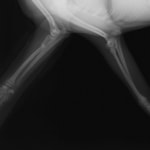

症例:交通事故による椎体脱臼

柴犬:9歳、避妊雌

交通事故直後、胸腰部に激しい疼痛、両後肢に完全麻痺を認め、シェフシェリントン徴候を呈していました。レントゲン検査において、第11-12胸椎間の脱臼が認められました。

脊髄の減圧、脊柱管の再構築・安定化を目的に、片側椎弓切除術およびMatrixMANDIBLE Plateによる椎体固定を実施しました。

隣接椎体を架橋するようにプレートを設置しました。

術後レントゲン写真